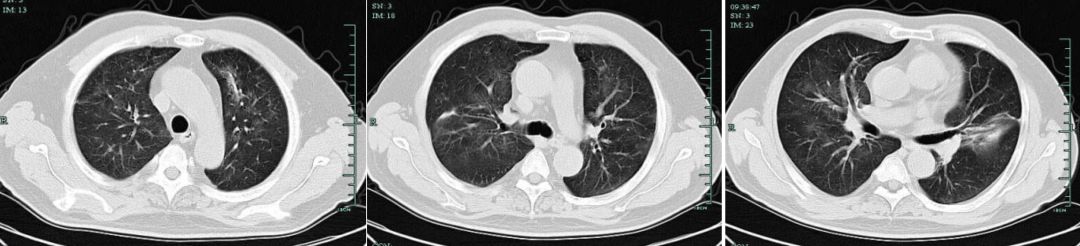

【图1】为11月1日肺部CT提示两肺弥漫淡薄渗出影

【图2】12月5日肺部CT复查提示两肺弥漫渗出影伴肺间隔增厚,较11.30明显进展